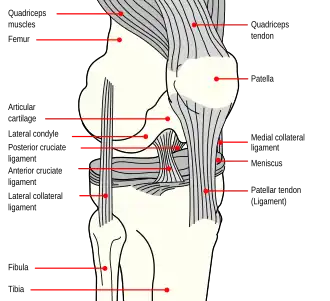

Надколенник (коленная чашечка) — самая крупная сесамовидная кость скелета человека. Располагается она в толще сухожилия четырёхглавой мышцы бедра, хорошо прощупывается через кожу, при разогнутом колене легко смещается в стороны, а также вверх и вниз. Верхний край надколенника скруглён и именуется основанием надколенника. Нижний край немного вытянут и образует верхушку надколенника. Передняя поверхность кости шероховата. Задняя суставная поверхность при помощи вертикально расположенного гребешка разделяется на две неравные части: меньшую — медиальную и большую — латеральную. У человека центр окостенения появляется в хрящевом надколеннике между 3 и 6 годами[1].

Основная функция коленной чашечки — защита от боковых смещений суставных поверхностей бедренной и большой берцовой кости, образующих коленный сустав. При сгибании и разгибании ноги коленная чашечка, расположенная внутри мощного сухожилия, смещается вверх и вниз по желобкам указанных выше костей, не давая им смещаться в стороны благодаря выступу на своей нижней (задней) поверхности. Кроме этого, по бокам коленного сустава имеются мощные крестовидные связки, которые обеспечивают дополнительную прочность сустава.